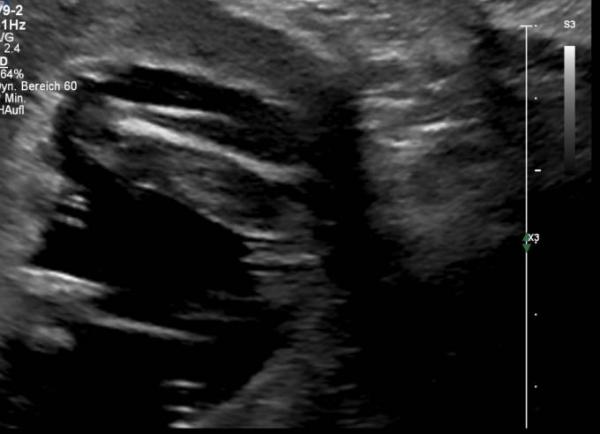

Hallöchen, auch ich hatte heute wieder einen FA-Termin. Dem Mäuschen geht es super, hat wieder viel gezappelt, ist 11 cm klein und hat uns auch einen Blick zwischen die Beinchen gewährt. Und was soll ich sagen, nach 4 Jungs bekommen wir endlich ein Mädchen Ich kann das noch gar nicht glauben.

Bild zu FA-Termin - Forum für Januar - Mamis